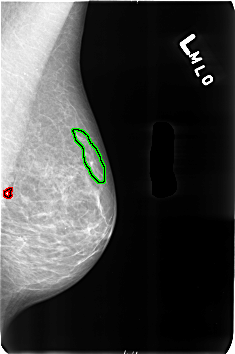

B_3164_1.LEFT_MLO

FILE: B_3164_1.LEFT_MLO.OVERLAY

TOTAL_ABNORMALITIES 2

ABNORMALITY 1

LESION_TYPE CALCIFICATION TYPE COARSE DISTRIBUTION N/A

ASSESSMENT 2

SUBTLETY 5

PATHOLOGY BENIGN_WITHOUT_CALLBACK

TOTAL_OUTLINES 1

BOUNDARY

ABNORMALITY 2

LESION_TYPE CALCIFICATION TYPE VASCULAR DISTRIBUTION N/A